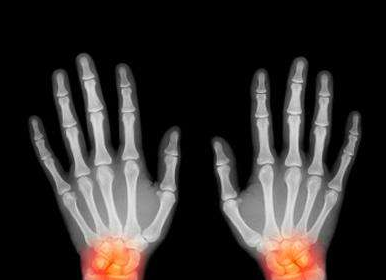

TF16010039 姓名:王先生 性别:男 年龄:41岁

- 病情

痛风 ①晚期 ②并发症 病史:12年+

- 治疗

治疗后手指关节、脚趾关节痛风石完全清除,血尿酸降至正常水平,手脚各关节痛感消失,关节活动恢复到正常状态。 ??